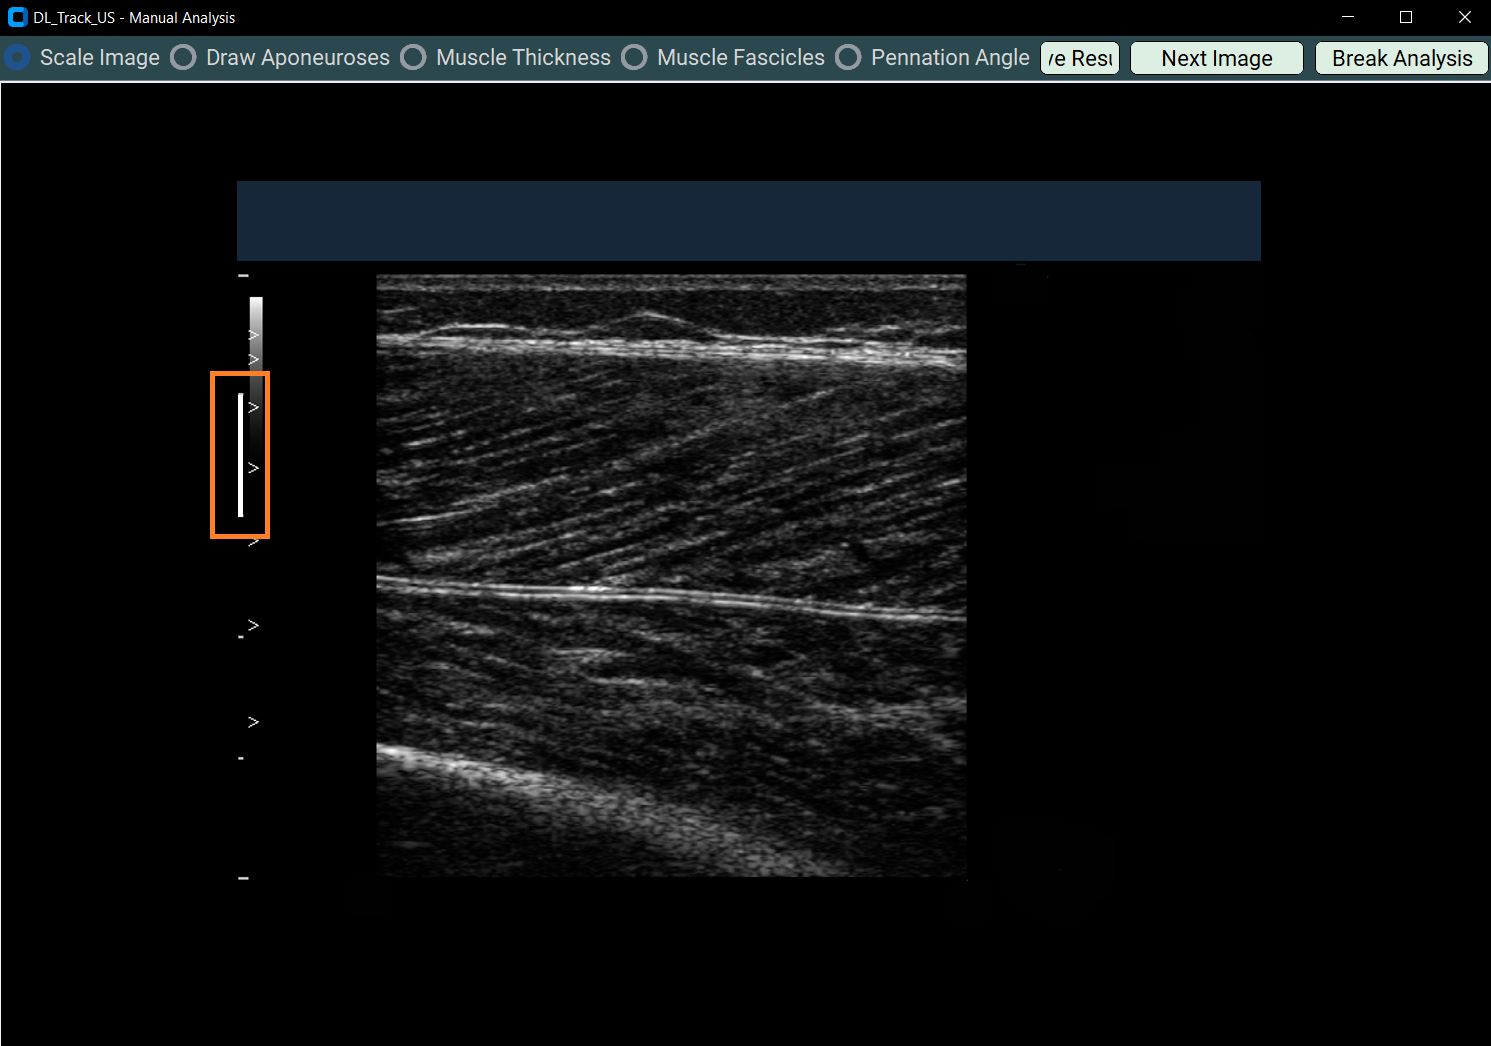

4.1 Manual Scaling¶

- Select Scale Image in the Manual Analysis window.

- Draw a 1-centimetre straight line based on scaling bars in the image.

- A messagebox will guide you.

Example of the drawn line: